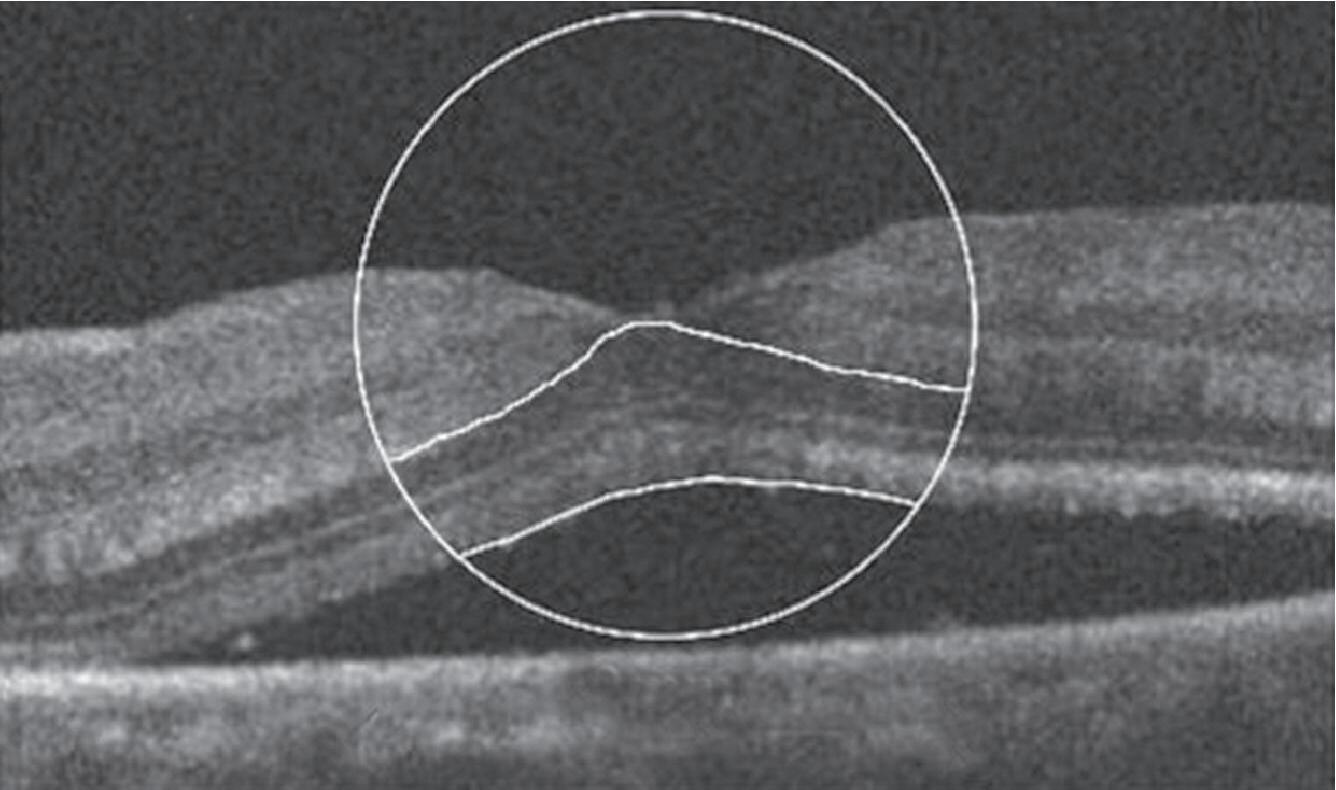

Um exemplo da capacidade da OCT para prever a acuidade visual pós-operatória em olhos com descolamento de retina regmatogênico (RRD) sem mácula está na Figura 1-27.20 Outras áreas da medicina se beneficiam igualmente da técnica da tomografia de coerências ótica . Para citar algumas: dermatologia no diagnóstico de lesões da pele como carcinomas etc. Na cardiologia se usa para obter imagens de alta resolução das artérias coronárias. O método de OCT por endoscopia foi introduzido em 1997 pelo pesquisador James Fujimoto no MIT e outros colaboradores. Finalmente, na indústria de semicondutores na medição não destrutiva das camadas finas dos seus dispositivos. O campo das aplicações do uso da OCT é cada vez mais amplo e se pode afirmar que novos e melhores equipamentos estão por vir.

1-27. Imagens pré-operatórias de tomografia de coerência óptica (oCT). Um círculo com um diâmetro de 2 mm foi posicionado manualmente no centro da superfície foveal da mácula destacada na imagem de oCT. a área macular dentro do círculo foi dividida em três seções: camada interna (superior direita: camada de fibras nervosas e camada de células ganglionares), camada intermediária (inferior direita: camada plexiforme interna e camada nuclear interna) e camada externa (inferior esquerda: camada plexiforme externa e camada nuclear externa). (reproduzida com permissão de https://www.hindawi.com/copyright/.)20